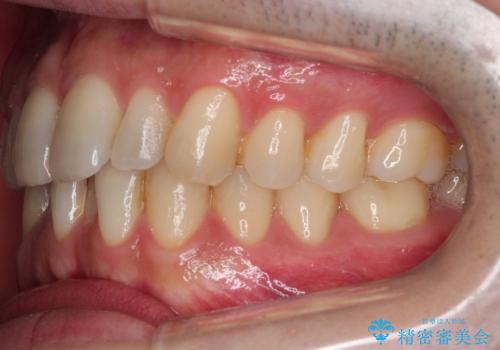

- 前歯の歯並びの改善を希望され来院された患者様です。

初診時の歯並びの状態としては、下顎に中等度のがたつき(叢生)がある状態でした。

抜歯は行わず下顎の奥のスペースを利用して歯をスライドする方法の他に親知らずの抜歯そして上下ともに歯列弓の拡大やディスキング(歯と歯の間の隙間を作る処置)を行い叢生を改善しました。

歯の大きさの不揃いが原因の正中のズレは、ディスキング量を調整することで合わせました。

矯正装置としてはマウスピースを使用しています。